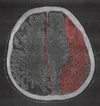

Eindrucksvoll ist was, siehe Fotos in der Bildergalerie klick unter dem Titelbild, eine Hirnblutung/Subdural/cSDH ist, und auch wie Dopplinger beschreibt diese nicht zwingend in einem cCT erkannt werden kann.

Der Patient der Ausgang meiner Recherchen war, hatte eine 3cm breite, die Mittelshift um 7mm verschiebende Hirnblutung, und das Kontroll cCT 3 Tage nach der Operation, beide cCTs wurden ihm und in den Arztbriefen verheimlicht, war 1cm breit und weitaus größer als das was in dem Bild als Hirnblutung/Subdural/cSDH dargestellte wird.

Da der Sonderfall des isodensen cSDH in der NativCT nur schwer erkennbar ist, kann im Einzelfall eine MRT-Bildgebung notwendig sein (1,3). Weiters kann ein bilaterales cSDH in der CT schwieriger zu erkennen sein, da im Gegensatz zum unilateralen cSDH die Symmetrie des Hirnparenchyms erhalten bleibt. Der Stellenwert der MRT-Diagnostik wird kontrovers diskutiert, sie gilt aber für Situationen mit Verdacht auf Subduralhämatom ohne eindeutige Hinweise in der CT als indiziert (2).